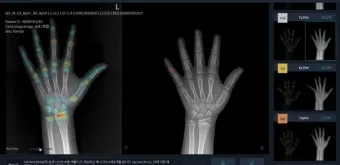

일반적으로 여성은 14-15세, 남성은 16-17세에 성장판이 닫히기 시작하지만, 완전히 닫히는 것은 만 19-20세경이에요. 하지만 여기서 중요한 건, 성장판 검사에서 '닫혔다'고 나와도 검사 오차가 있을 수 있고, 미세하게 남아있는 성장판으로 인한 성장 가능성이 남아있다는 점입니다.